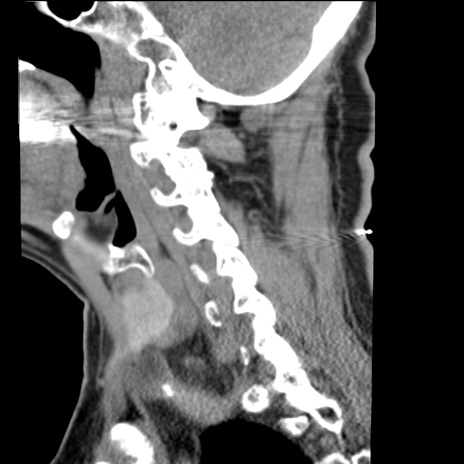

症例50 頚椎CT(矢状断像)

【症例】60歳代女性

【主訴】後頭部〜右後頸部にかけての痛み

【現病歴】本日飲食店でコーヒーを飲んでいたところ、突然後頭部〜右後頸部にかけて痛みが出現し、右上肢の感覚障害を伴ったため救急要請。

【身体所見】脳神経学的に明らかな異常所見を認めず。右上肢に軽度の感覚障害あり。

冠状断像